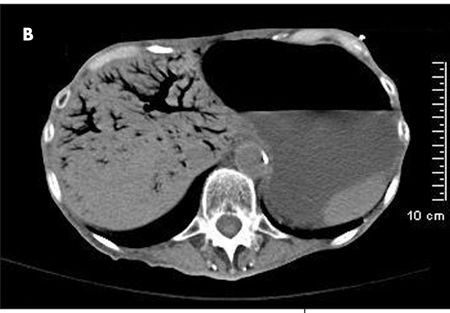

The patient complained of diffuse abdominal pain. She had an erythematous swelling around the right iliac fossa, abdominal guarding, and palpable crepitations. CT scan of the abdomen without contrast showed extensive portal venous air from the small branches in the periphery to the main portal and splenic veins (A and B). Considerable gaseous distention of the small bowel (C and D) and dilated loops of the small bowel were also seen (D and E). These findings were consistent with pneumatosis intestinalis.